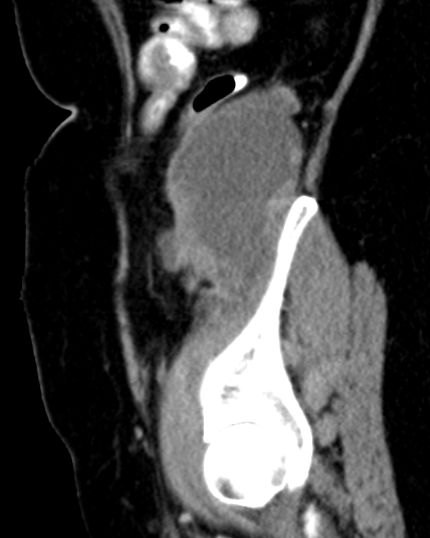

| Diagnostik | partiell nekrotisches, pleomorphes undifferenziertes Sarkom der Bauchwand.![]() |